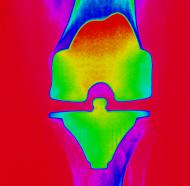

• Avköna knäet - Att övervärdera könsskillnader som ett problem

Avköna knäet - Att övervärdera könsskillnader som ett problem